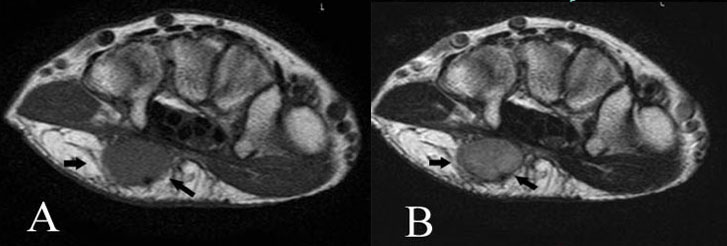

A 52-year-old man had dysesthesia of left ring and little fingers of three-year duration and a soft tissue mass in the left palm of six months duration.

On physical examination, a rubbery mass with skin bulging in the left palm was palpable, which measured a size of 22 mm × 25 mm using vernier caliper. There were no changes of the skin including heat, red flare, ulcer, and pigmentation. Spontaneous local pain was not identified, but tenderness on the tumor was observed. MRI showed a well-circumscribed mass in the subcutis and attached to the palmar aponeurosis that had homogeneous intermediate intensity on T1-weighted image and inhomogeneous high intensity on T2-weighted image (Figure 3A and Figure 3B). Clinical and radiological differential diagnoses include hemangioma, neurogenic tumor, synovial sarcoma, and clear cell sarcoma. Excisional biopsy was performed using air tourniquet under general anesthesia. The tumor was located within the subcutis. The tumor capsule was not identified and the border was unclear in place. Macroscopically, the tumor surface was whitish and fibrous appearance. The palmar branch of ulnar nerve was identified the bottom of the tumor. The nerve was gently detached from the tumor using blunt dissection.

Figure 3: Case 2. Angiofibroma of soft tissue in the palm. Axial T1-weighted MRI (TR/TE=529.63/23) demonstrates a well-circumscribed subcutaneous mass adjacent to the palmer aponeurosis with homogeneously slightly high signal intensity (black arrows) (A). Corresponding axial T2-weighted image (TR/TE=2652.90/83.85) reveals a mass to be inhomogeneously high signal intensity (arrows) (B).